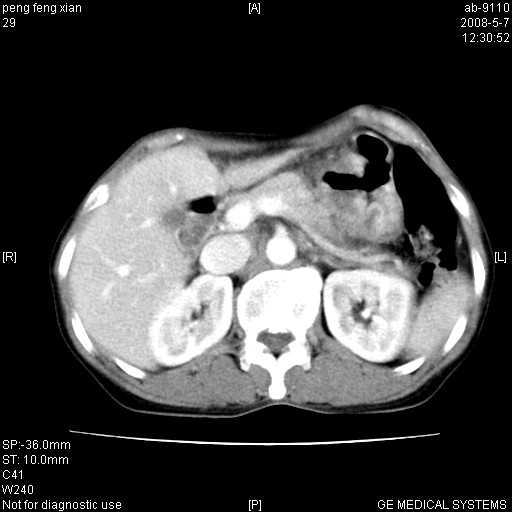

女,56岁。b超左一腹包块,考虑胃肠道肿瘤。

胃体部胃壁增厚,不均匀性强化,与胰腺分解欠情.

考虑:胃癌,胰腺受侵待除外.

鉴别:胃淋巴瘤(强化不明显)

建议:胃镜检查.

典型胃癌胰体尾部受侵。

胃壁增厚,左前胸壁局限性隆起,考虑胃癌可能性大,建议做胃镜